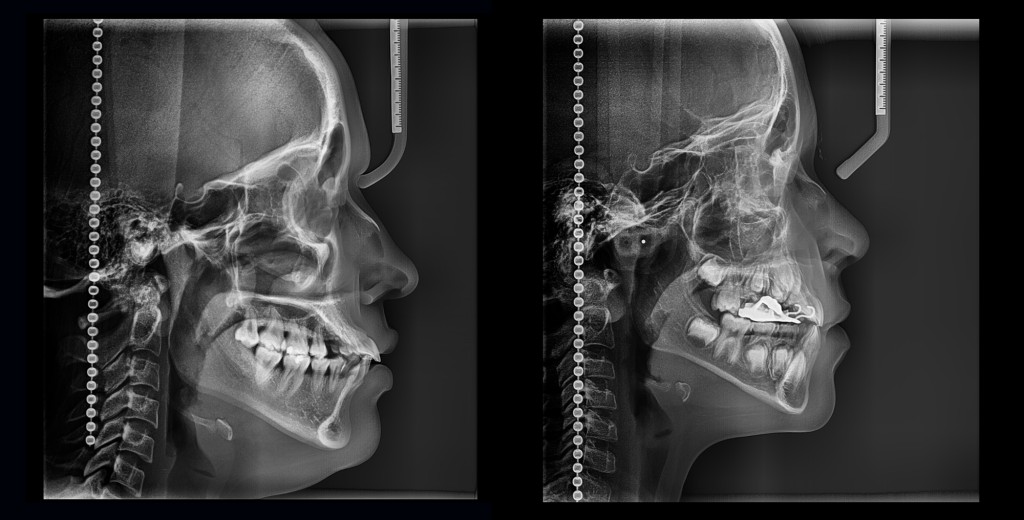

CEFALOMETRIA LATERAL

• El cefalograma lateral no es solo una radiografía, este te permite moldear confianza, auto estima y armonía facial.